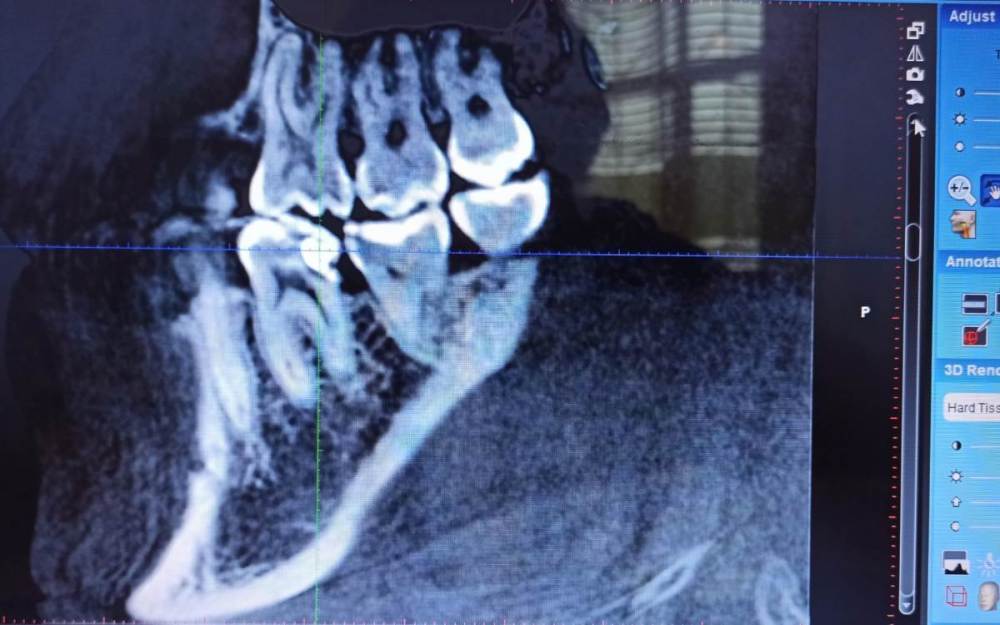

Снимки из КТ 2019-го года, и рентген лета 2022г.

Пломба ~2015-го.

@IvanK такие истины понятны, но вот напрягает, что уже на КТ старом вижу,что как будто пломба прямо на пульпе ...и тогда то ли я вижу совсем не то,то ли действительно так - и значит что снимая эту пломбу, точно же придется "умерщвлять"?

То есть кроме того снаружи видно что пломба большая и кариес под нее "подлез", увидел эту непонятную темноту, как будто пульпу, переходящую в пломбу и напрягся так сказать